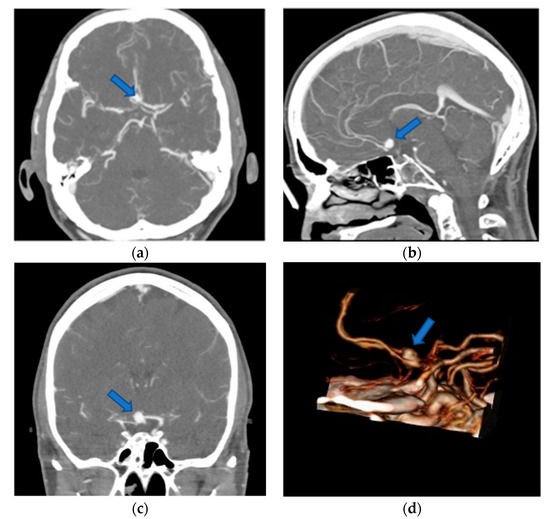

3.2.1. Impact on Identification of Anatomical Structures